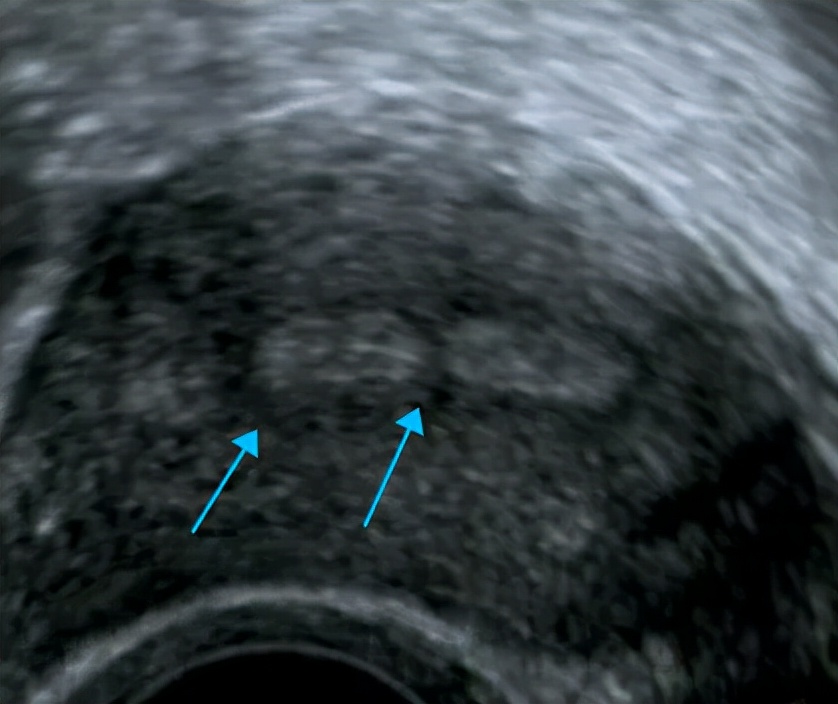

内膜本该连续的地方却见到一处连续性中断的地方

箭头所指就是粘连处

这都是在内膜有一定厚度和形态且粘连程度较明显的情况下,超声可以看到的间接征象。现在不止二维的超声可以检查宫腔粘连,三维超声也可筛查出宫腔粘连。